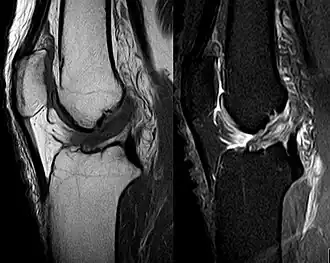

MRI shows normal signal of both cruciate ligaments (arrows) -